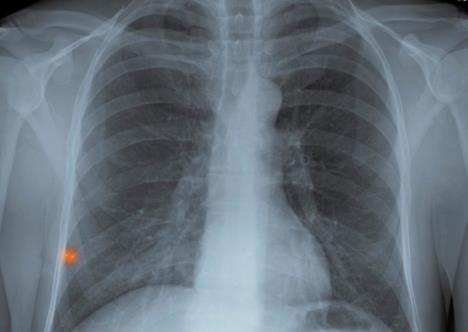

Vest o teškoj bolesti kolege uznemirila je zaposlene u opštini pa su svi članovi saveta upućeni lekaru. Oni će morati na rentgenski pregled pluća, ali će i članovi njihovih užih familija, kao i osobe sa kojima su bili u bliskom kontaktu biti upućeni na snimanje.

Tubekuloza je zarazna bakterijska bolest koja posebno utiče na pluća. U Austriji se godišnje zabeleži 600 slučajeva ove bolesti. Pošto ne postoji vakcinacija, osobe inficirane ovom bakterijom neophodno je što pre otkriti, kako bi lečenje počelo na vreme.